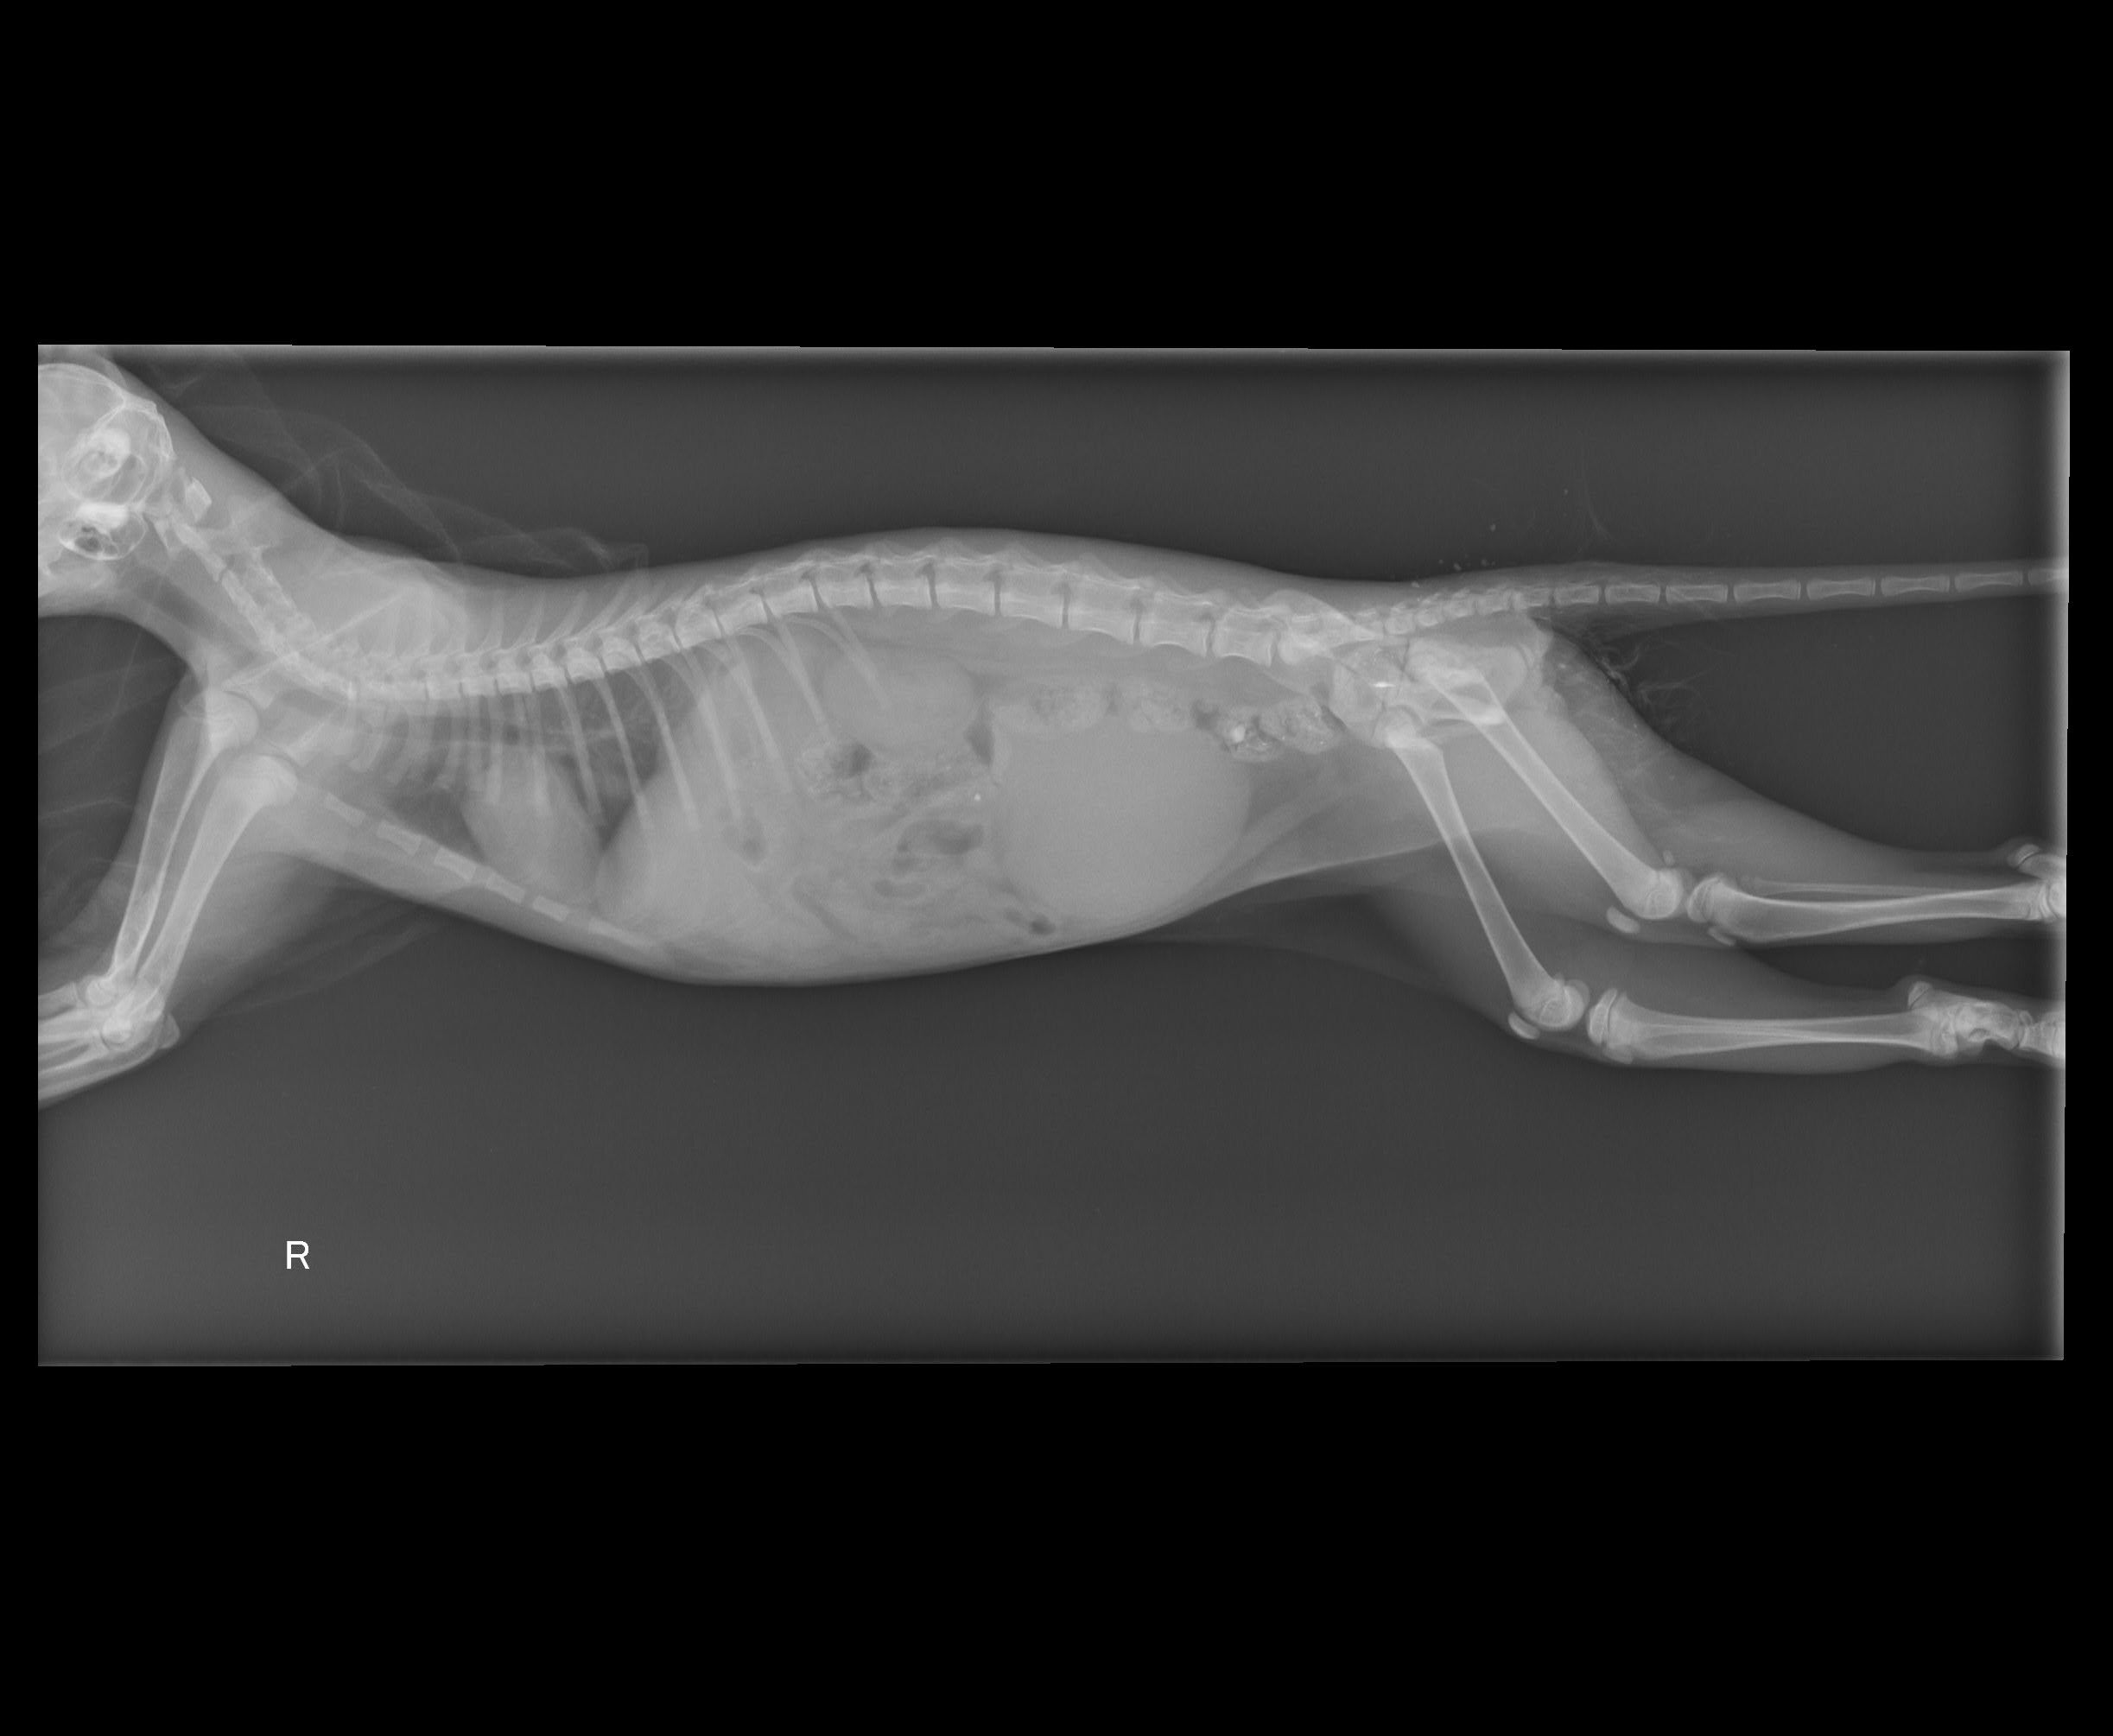

回去傳雞絲頭叩幫手等等集合,到達附近後,兩人開始分頭尋找,這時小幫手即時傳來最新訊息,知道了正確地點,二話不說地直奔,停好車開始尋找,ㄟ∼車底下那隻是…,對照一下資料照,賓果!!是牠了,好小一隻,怎麼是小貓?資料照片看起來像成貓呀?!好心疼,牠好瘦用著兩隻前腳支撐著坐在車底∼先開罐頭測試,很好!不吃∼這時緊張的牠開始想爬進車底裡,哎呀~不行!於是顧不得一切,趕快趴到車底下徒手抓住牠還露在外面的下半身,拉呀拉地抓出了牠,進籠吧!《小朋友你要加油喔》心裡默念著∼動物近況說明: 阿妹牠的X照脊椎沒斷,但就是站不起來,經過幾天治療與觀察,醫生說牠站起來的機率很低,而且後腳有開始萎縮的現象,對於所有疼痛測試皆無反應,而牠也無法自行大小便要人工擠,醫師說之後再試試針灸治療看看,希望針灸有效,牠還那麼小,真不希望是如此的結果發生。阿妹有找到願意照顧她的認養人帶回安置照顧,之後的針灸或其他醫療費用認養人願意自行負擔。